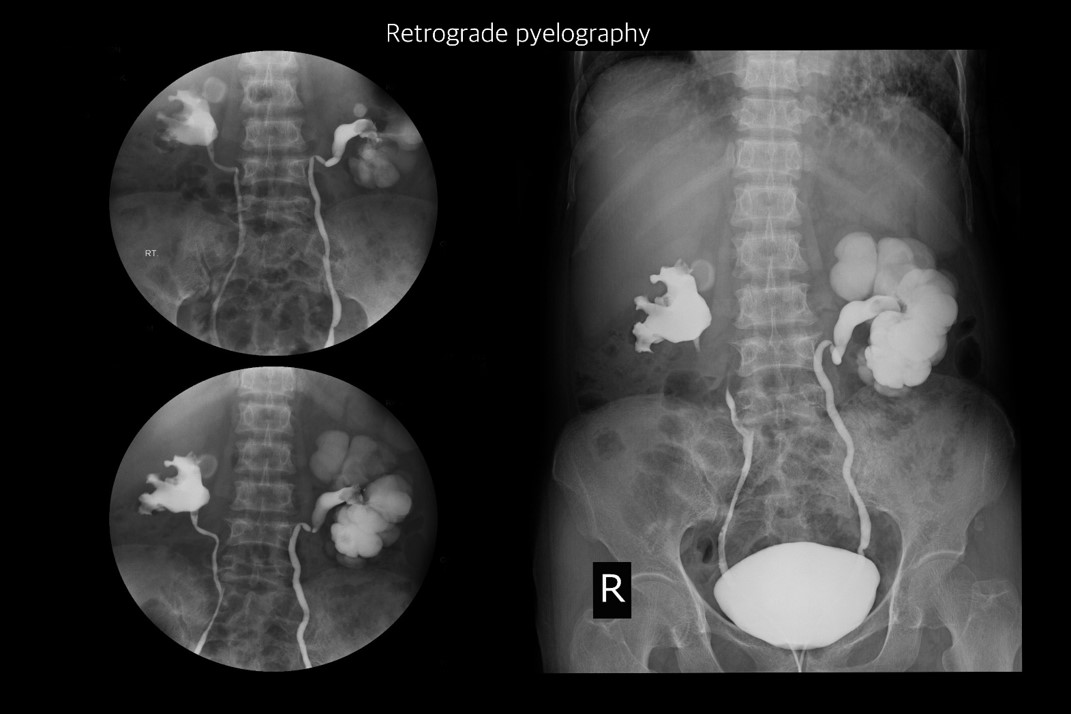

靜脈注射腎盂攝影術(IVP):注射顯影劑後,透過X光顯示腎盂、輸尿管和膀胱結構,評估尿路是否阻塞、結石大小與位置,並可偵測腎乳頭壞死、尿路逆流及慢性腎盂腎炎。